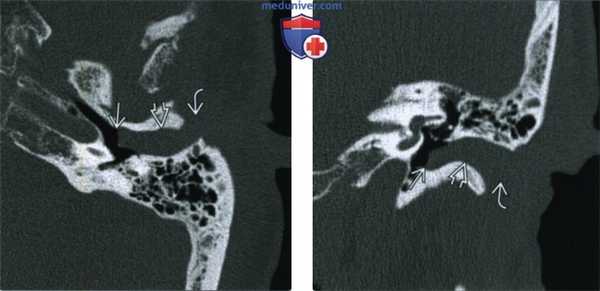

(Слева) При аксиальной КТ в костном окне левой височной кости визуализируется НСК, заполненный мягкими тканями. Этот компонент, выглядящий мягким, расположен снаружи от барабанной перепонки и достигает хрящевой части НСК.

(Справа) При корональной КТ в коаном окне у этого же пациента определяется мягкотканный компонент в НСК, выглядящий доброкачественным, расположенный снаружи от барабанной перепонки и достигающий хрящевой части НСК. Определяется легкое коническое расширение костной части НСК снаружи, но других явных изменений костей не выявлено.